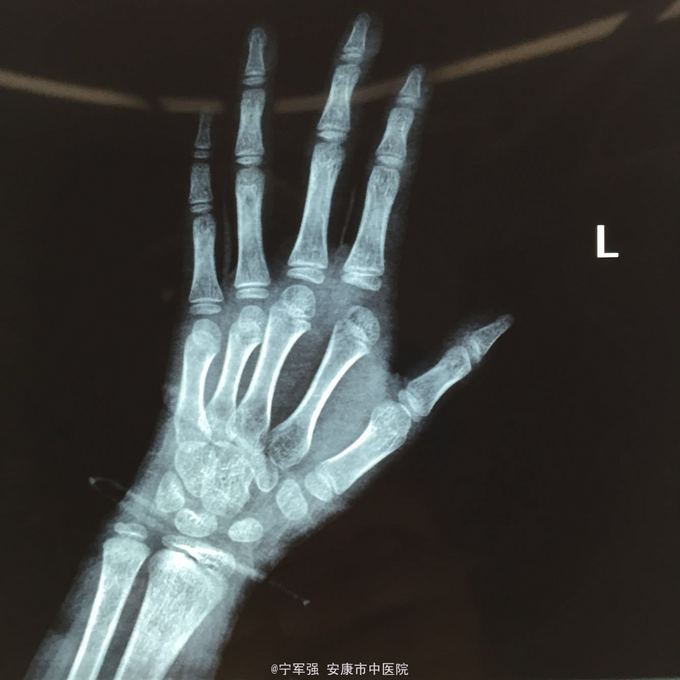

患者8岁,女 扭伤致左手食指肿痛活动受限2小时

患者一般情况良好,左手第二掌指关节处肿胀,弹性固定于伸直位,活动受限,压痛明显,循环尚可

诊断:左手第二掌指关节脱位 处理,予以手法复位失败!考虑关节囊坎顿,阻止复位 予以局麻小切口探查证实,复位脱位,修补关节囊

指骨夹板固定,复查x线显示复位良好 随诊